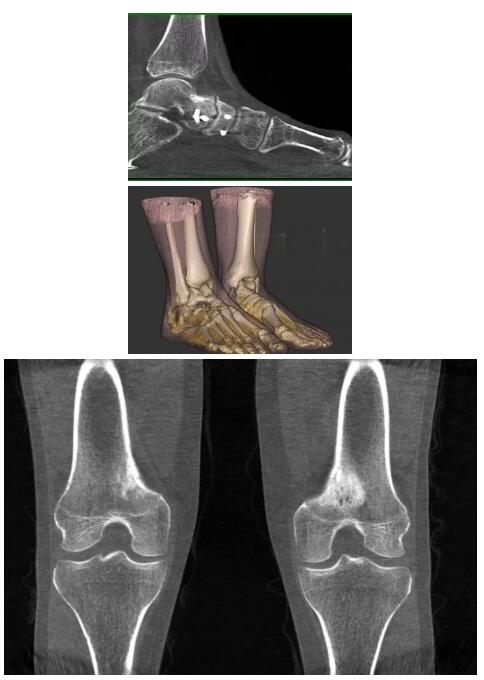

比如上面這款專用于足部和踝部掃查的CT成像系統(tǒng),患者在進(jìn)行CT掃查時(shí)只需要站在上面即可,雙腳站或者單腳站都可以,當(dāng)然,如果患者不是那么方便站著做完CT掃查,也可坐在上面。

這款CT掃查系統(tǒng)自帶屏蔽裝置,它的體積非常小,僅需要極小的空間即可,并不像常規(guī)CT那樣需要一間單獨(dú)的檢查室。此外,這種CT掃查的速度非???,僅需30秒左右可以完成檢查,輻射劑量相對(duì)常規(guī)的CT要少許多,尤其適合醫(yī)院的骨科使用。

而患者站著做足部或者踝部做CT檢查還有個(gè)好處是,可以檢查患者在負(fù)重的情況下,骨關(guān)節(jié)的真實(shí)情況,而躺著做CT掃查時(shí)未必能看出來(lái)。負(fù)重CT掃查特別是對(duì)于受傷的運(yùn)動(dòng)員或者舞蹈員來(lái)說(shuō)意義更大,能夠更準(zhǔn)確地評(píng)估傷情,幫助他們盡早復(fù)原。

另外一款被稱為世界上最小的CT,它的重量?jī)H300磅,不僅能夠掃查足部,還可以檢查膝蓋和上肢等。

與上面介紹的CT一樣,它同樣具有輻射低、占地空間小(23*36)的特點(diǎn),隨開(kāi)隨用(支持直接接入墻上的插座)。

這款CT使用非常方便,通過(guò)上下移動(dòng)保持與患者的手臂或者雙腿齊平,掃描快速,僅需要30秒左右就可以完成掃查。

以上介紹的CT均來(lái)自國(guó)外同一家公司,這些CT均配置了可視化軟件,可以進(jìn)行切片、3D重建以及大型CT附帶的所有典型的操作功能。

以下是這些“特立獨(dú)行”的CT所拍出來(lái)的圖像: